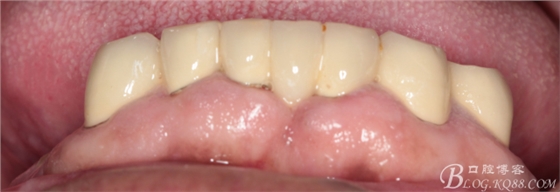

修復(fù)兩年后患者復(fù)診

44作為覆蓋基牙保留完好,牙周狀態(tài)良好,附著體基牙有一定的牙齦萎縮,

上頜套筒冠基牙無松動(dòng),對(duì)比做牙前得到較大改善

下頜附著體 義齒有菌斑殘留

上頜義齒有煙斑殘留